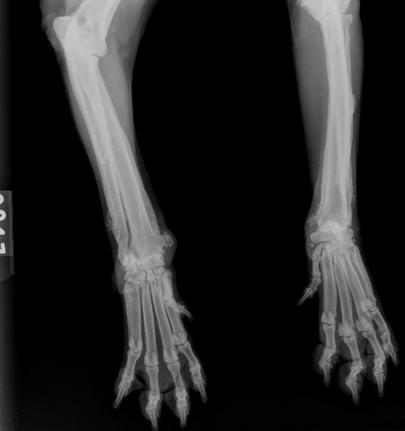

El control radiográfico realizado aproximadamente 23 meses después mostró lesiones periósticas en distal de miembros anteriores con aspecto más liso, radiodenso y con disminución del tejido blando circundante, lo cual sugeriría un estado de inactividad perióstica (Figura 3). En la radiografía torácica no se evidenciaron alteraciones.

Figura 3: Radiografía de control de los miembros anteriores a los 23 meses luego del diagnóstico de osteopatía hipertrófica. Se observa lesiones periósticas en distal de miembros anteriores con aspecto más liso, radiodenso y con disminución del tejido blando circundante, lo que sugiere menor agresividad.